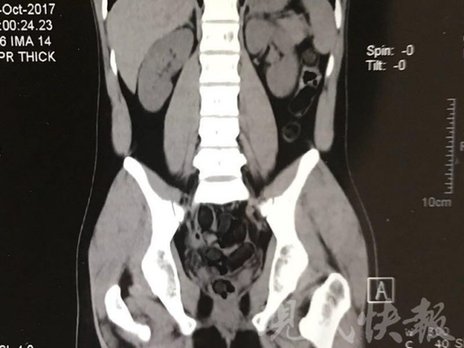

运毒小伙:希望被判处死刑

由于毒品在体内一旦泄露有可能致命,警方第一时间将阿永带到医院进行检查。CT 扫描的结果显示,阿永体内布满了密密麻麻的白色圆柱状固体,就像一粒粒的蚕蛹。在南京市公安局鼓楼分局二板桥派出所,阿永分四次排出了毒品,毛重369.99 克。经讯问,阿永交代了自己全部的犯罪事实。目前,阿永已被刑事拘留。